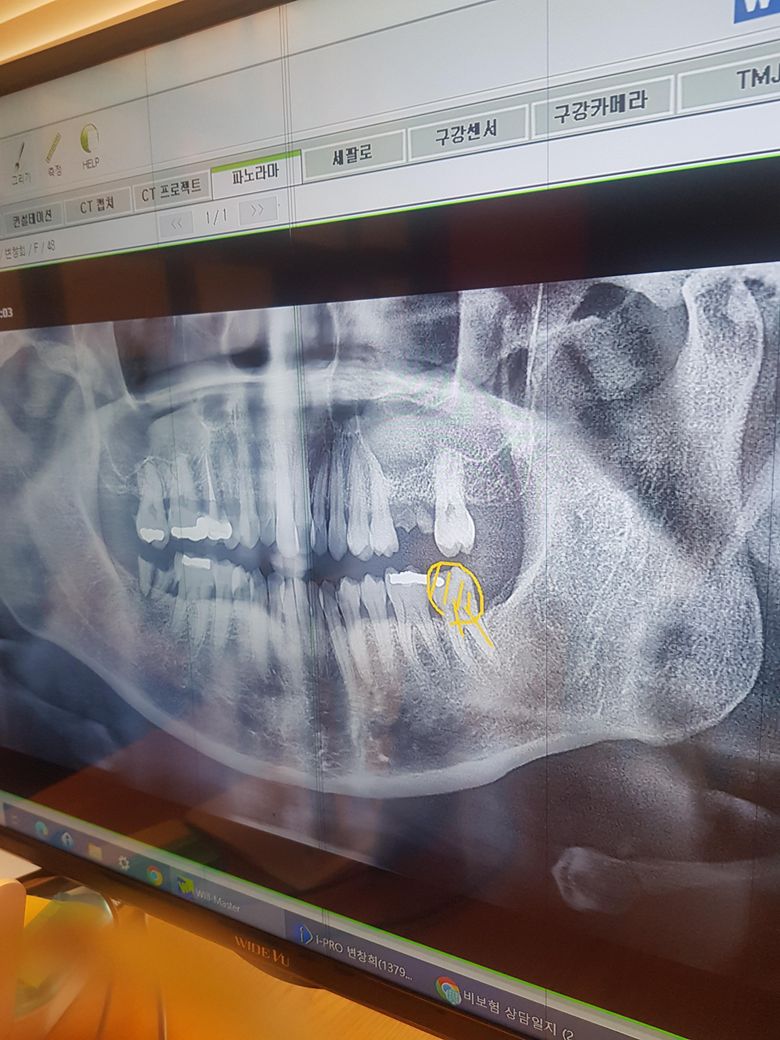

위어금니옆에 파절된지 몇년지났는데 그쪽으로 씹어도 안아프길래 병윈안가다가아래어금니 48번아말감이 일부깨젰는데 아파서 병원갔는데 실장님이 윗쪽은 무조건 임플란트하고 뻐이식비용이 50든다고 하는데요. 아직48세인데 뼈이식을 꼭해야하나요? 뼈가부족한지 안한지 어떻게알까요?전브릿지하고싶은데 실장님은 임플란트 강추하세요 ㅠ 아직임플란트는 안하고싶은데 사진첨부합니다. 조언부탁드레오

• 1번 째 사진

파노라마 상으로는 뼈가 어느정도 임플란트 심기에는 충분해 보이지만 정확한건 CT를 찍어보셔야될것같습니다.

1. 일단 설명들으신 부분은 20번, 30번대 치아입니다. 파노라마 사진상에서는 좌우대칭입니다. 사진상 오른쪽이 실제로는 왼쪽 위, 아래입니다.

2. 20번대 (실제 왼쪽 위) 어금니 부위는 브릿지도 가능하지만 임플란트가 더 최신 술기이긴 합니다. 다만, 상악동이라는 위턱뼈 빈 공간 구조가 잇몸뼈 부위쪽으로 침범해서 뼈이식은 불가피할 것 같습니다. 임플란트와 브릿지는 상황에 따라 각기 장,단점이 있습니다. 수술이 싫고 브릿지를 강력히 원한다면 다른 치과를 알아보는 것도 좋습니다.